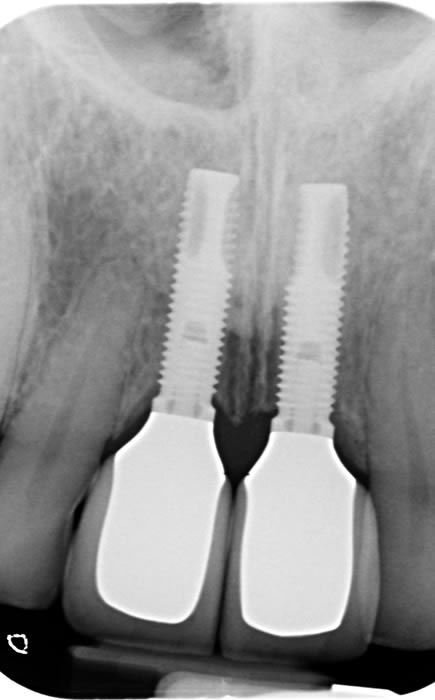

More front teeth replaced by dental implants

Case Three (4 images)